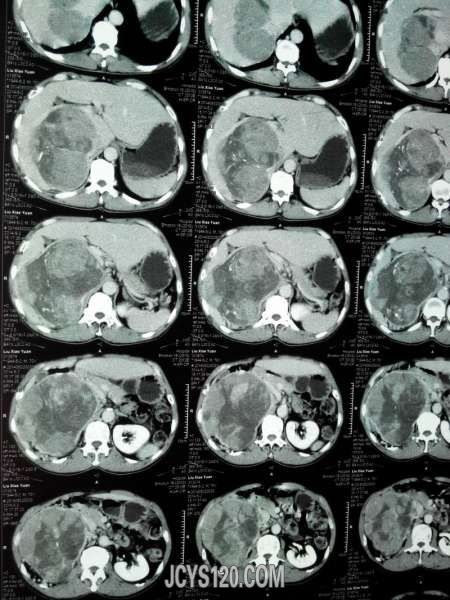

患者女性,70岁,体检发现,大家诊断什么病,怎么治疗。谢谢!